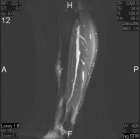

21 year old male with increasing leg pain and enlarging mass for three years